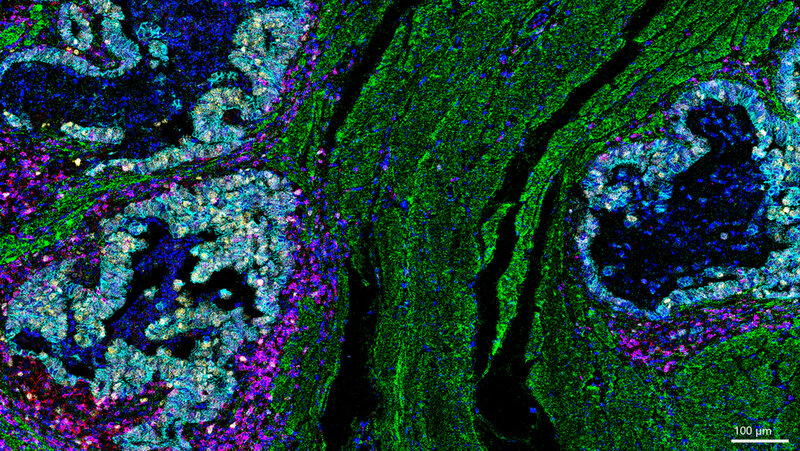

„Unsere Daten zeigen, dass die Reaktion des Immunsystems entscheidend mitbestimmt, wie gut eine Therapie wirkt – selbst wenn der Tumor sich genetisch kaum verändert“, sagt Co-Studienleiter Prof. Dr. Michael Quante, Leiter des Zentrums Gastrointestinale Tumore der Klinik für Innere Medizin II am Universitätsklinikum Freiburg. Für die Studie wurden Gewebeproben von 27 Patientinnen und Patienten mit lokal fortgeschrittenem Speiseröhrenkrebs untersucht. Alle hatten eine sogenannte neoadjuvante Therapie erhalten – also eine Behandlung vor der Operation, meist in Form einer Chemotherapie oder kombinierten Strahlen-Chemotherapie. Dabei zeigte sich: Die Krebszellen selbst blieben erstaunlich stabil. Die Veränderungen fanden vor allem im Umfeld des Tumors statt – in den Immunzellen, dem Bindegewebe und den Signalwegen zwischen Zellen.

Besonders auffällig war: In Tumoren, die schlecht auf die Therapie ansprachen, fanden die Forscherinnen und Forscher Hinweise auf eine sogenannte Immunflucht. Dabei verändere der Krebs bestimmte Oberflächenmerkmale, um vom Immunsystem nicht mehr erkannt zu werden. Auch hemmende Signale wie das Molekül PD-L1 seien bei diesen Patientinnen und Patienten erhöht gewesen. Diese Signale gelten als mögliche Ziele für moderne Immuntherapien. Die Untersuchung wurde im Rahmen der MEMORI-Studie durchgeführt, an der mehrere Standorte des Deutschen Konsortium für Translationale Krebsforschung (DKTK) beteiligt waren – darunter München, Freiburg und Essen. Eine zentrale Komponente der Studie war die Analyse der Tumorevolution unter Therapie mittels Gensequenzierung, die zusammen mit Co-Studienleiter Prof. Trevor Graham, Direktor des Centre for Evolution and Cancer am Institute of Cancer Research in London, im Rahmen eines Krebshilfe Mildret Scheel Stipendiums für Dr. Melissa Barroux durchgeführt wurde.